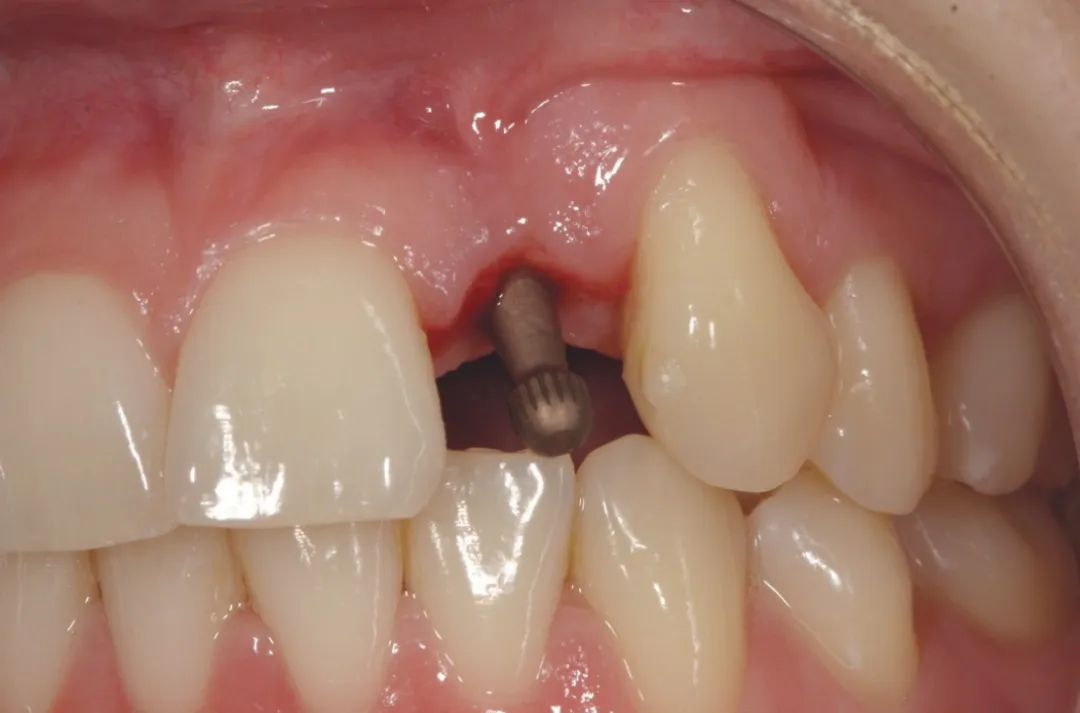

3 号病例 - Patrick EXBRAYAT 医生(图 36 至 49)

女性患者,侧切牙 12 发育不全,长期使用临时修复手段。

图 38 :拔牙后种植位点。

图 39 :种植体就位。